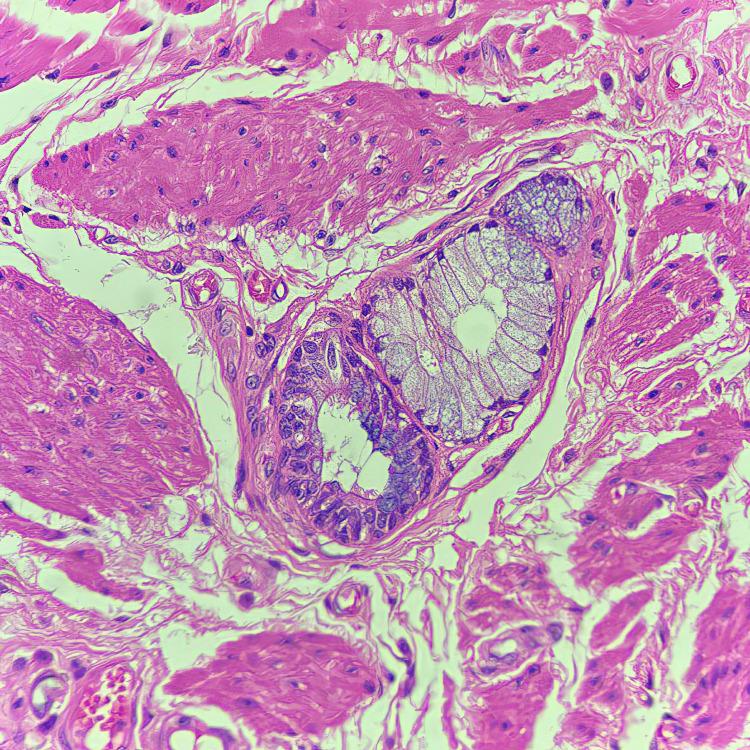

Tracheobronchial rests are a rare congenital anomaly where ectopic respiratory tract elements may be found in an abnormal site, such as within the esophageal wall. We present a case of a late presentation of an esophageal intramural tracheobronchial rest with complaints of pain in the left chest wall, vomiting, and loss of appetite for one month. The chest X-ray and mammogram were both normal, but an endoscopy could not be performed due to luminal narrowing. A CT scan shows a well-defined, round, non-enhancing hypodense lesion measuring 2.6 x 2.7 cm in the middle one-third of the esophagus. Upon resection, histopathological examination revealed fragments of tissue lined by pseudostratified ciliated columnar epithelium with respiratory mucinous glands admixed with pools of mucin and underlying strands of skeletal muscle. The subepithelium contains esophageal submucosal glands, which confirm the esophageal origin of the choristoma. The usual presentation is congenital esophageal stenosis at birth with over half of these cases being attributed to tracheobronchial rests. Presentation beyond adolescence is even rarer with a relatively benign course and favorable prognosis. Clinical, radiological, and pathological correlation as well as a high index of suspicion are important to avoid misdiagnosis and to institute optimal treatment.